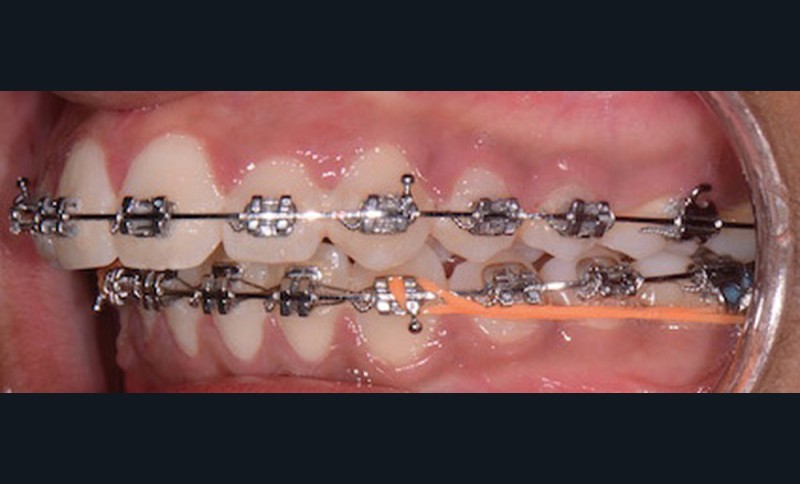

Nous équipons la patiente avec un appareil multi-attaches (.022 x .028 inch pré-informé Roth) mais nous n’avons pas activé l’arcade mandibulaire. La patiente est adressée au chirurgien maxillo-facial (Dr Gonzague Deffrennes, hôpital Beaujon) qui réalise l’avulsion des troisièmes molaires et la pose de plaques vissées avec émergence entre les premières et deuxièmes molaires mandibulaires dans l’axe des brackets (fig. 9). Étant donné l’absence d’encombrement au niveau incisif mandibulaire, nous pouvons rapidement mettre en place les tractions postérieures. Nous solidarisons ainsi le bloc antérieur de canine à canine et réalisons un recul en masse de l’arcade directement des canines aux plaques postérieures. La majeure partie du recul est faite sur un arc acier .018x.025 inch permettant le glissement. La force appliquée est de 250-300 g par côté.

Nous avons pu repositionner l’incisive mandibulaire de 8° (fig. 10), obtenir un surplomb correspondant à la classe II d’Angle et ainsi réaliser l’avancée mandibulaire. Le chirurgien accompagne celle-ci d’une génioplastie afin d’harmoniser le profil. Nous corrigeons la DDD par stripping des incisives mandibulaires ce qui permet de corriger encore de 1° l’axe incisif.